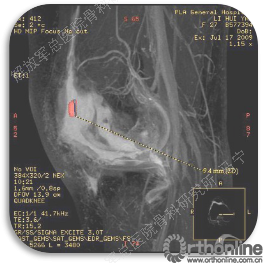

首先经过核磁的检查、评估,初步确定软骨损伤范围,利用T2maping检测序列对软骨的信号区分。图中我们可以看到软骨损伤的范围,并通过计算机计算出大概的面积。

虽然是软骨损伤,但也需要X线评估关节结构,测量双下肢力线,髌骨轨迹,Q角等,排除结构因素引起的软骨损伤,若术前存在发育不良,脱位,半月板损伤,交叉韧带损伤,必须先进行矫形,最后再进行软骨修补,才能达到最佳效果和持久性。

软骨缺损范围的测量。

姜**:男,33岁 ,双膝疼痛,活动受限1年,曾经打过玻璃酸钠,效果都不理想,来我院行软骨修补术,MRI显示髌骨软骨下骨增生明显,并开始磨损滑车。

术后3个月在当地医院复查MRI,软骨补片与正常软骨还存在GAP现象,冠状位隐约还能看见周围的轮廓。

术后6个月复查MRI,软骨修复的已经具备一定的厚度,软骨下骨没有明显水肿。增生的软骨下骨被去除后没有再进一步磨损滑车软骨。